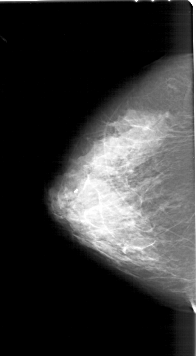

FILE: A_1218_1.RIGHT_CC.OVERLAY

TOTAL_ABNORMALITIES 1

ABNORMALITY 1

LESION_TYPE MASS SHAPE LOBULATED MARGINS ILL_DEFINED

ASSESSMENT 4

SUBTLETY 2

PATHOLOGY MALIGNANT

TOTAL_OUTLINES 1

BOUNDARY

LEFT_CC LINES 6406 PIXELS_PER_LINE 3526 BITS_PER_PIXEL 12 RESOLUTION 43.5 NON_OVERLAY